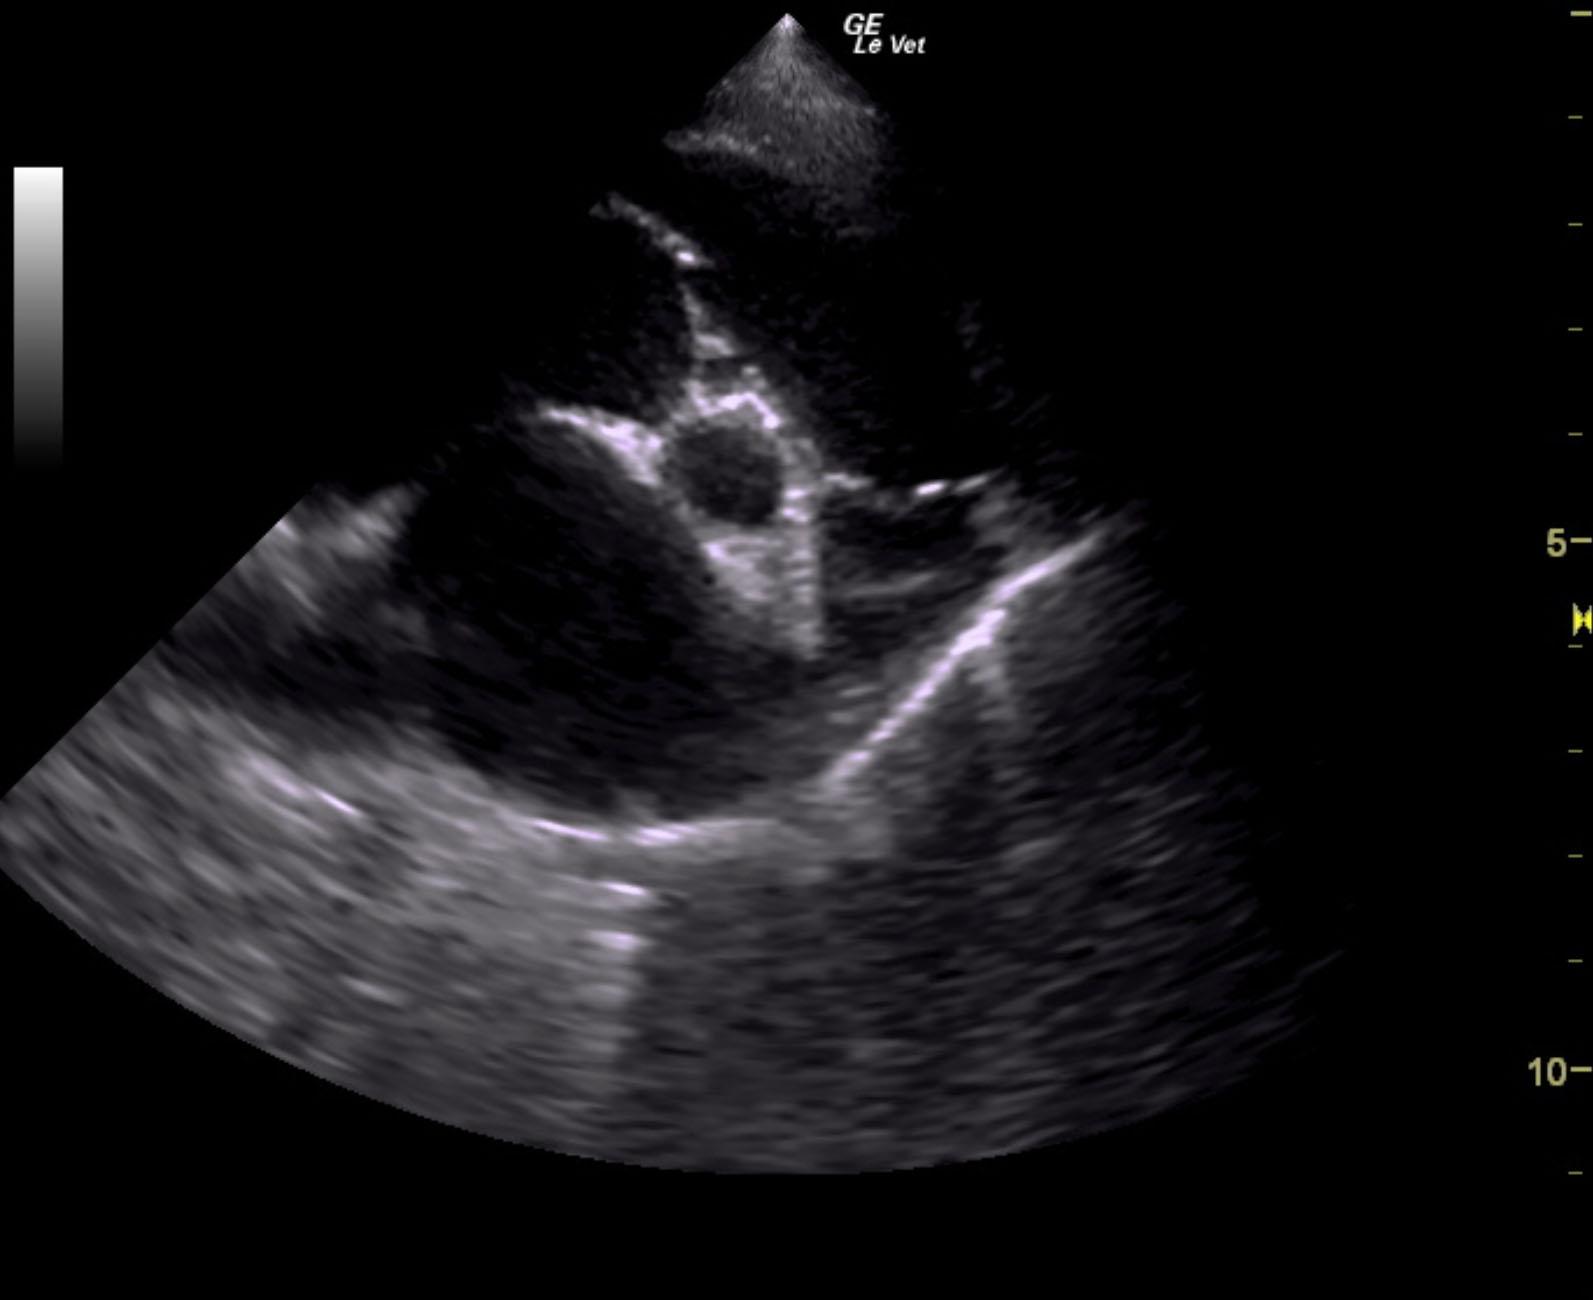

The cardiac presentation revealed moderate left and right sided overload with tricuspid and mitral valve vegetative lesions. Left atrial and right atrial enlargement was noted. Right ventricular overload was noted with flattening of the ventricular septum. Slight prolapse of the anterior mitral valve leaflet was noted. Prolapse of the tricuspid vavle was also noted. Significant pulmonic insufficiency and tricuspid insufficiency was noted. This is consistent with pulmonary hypertension.